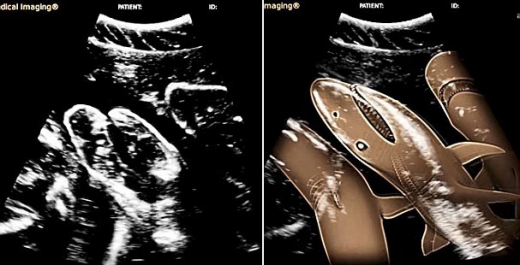

세계 최초로 새끼를 가진 뱀상어의 초음파 영상이 공개돼 학계의 관심이 쏠리고 있다. 뱀상어(tiger shark)는 줄무늬가 호랑이 무늬를 닮았다 해서 호랑이상어로도 부르며, 태평양과 대서양, 인도양의 열대 온대 해역에 분포한다. 야행성으로 몸길이는 최대 6m까지 자란다.

미국 마이애미 대학교 로젠스틸 캠퍼스와 호주 뉴잉글랜드 대학교 해양학 공동 연구진은 지난 2001년부터 3년간 카리브해 바하마의 일명 ‘타이거 해변’에서 ‘에밀리’라는 이름의 암컷 상어를 관찰해왔다. 에밀리는 몸길이 약 4m 정도이며, 연구진이 초음파 촬영을 시도한 당시 에밀리는 뱀상어의 평균 임신기간(12~13개월) 중 3분의 2 가량이 지난 상태였다.

연구진이 해양 첨단장비를 이용해 에밀리의 뱃속을 초음파 촬영한 결과 에밀리의 배에는 총 20마리의 새끼가 자라고 있었으며, 이들은 각각 40~45㎝정도의 몸길이로 매우 건강한 상태였다.

또 초음파 촬영을 통해 뱃속 새끼 상어들의 지느러미와 눈, 이빨의 배열 등도 자세히 확인할 수 있었다.